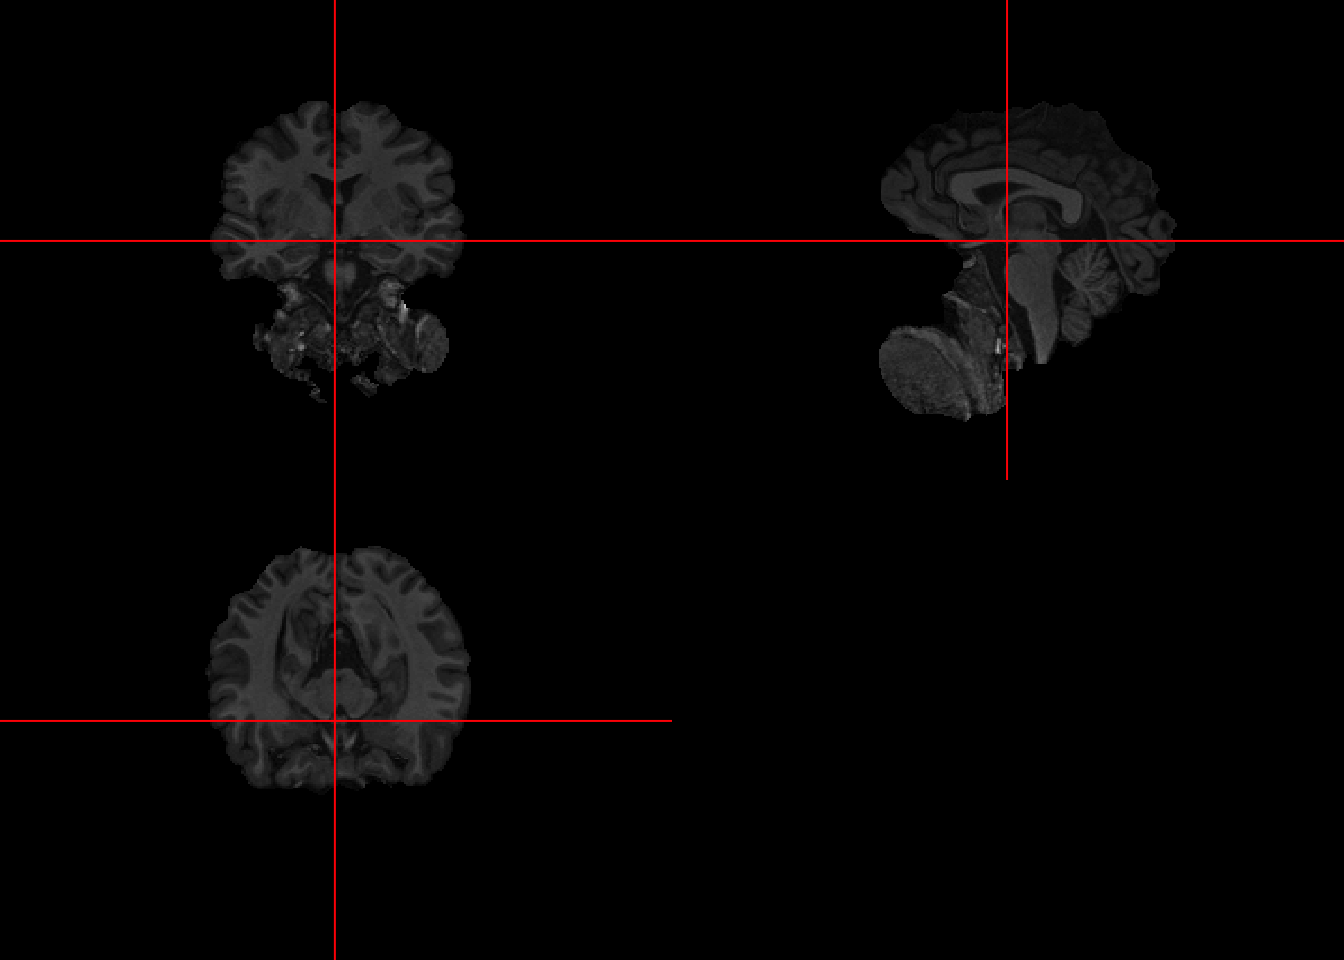

7.3 Visualizing first past

To visualize the effects of the brain extraction on the original, the orthographic may be used twice by passing (1) the image returned by BET, (2) the original image overlaid by a mask. To produce the mask, follow the code below.

orthographic(bet_fast)

The results are not great since a lot of non-brain areas get included.